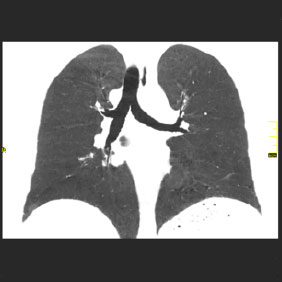

Tomografía computarizada Tórax

< Volver a "Tomografía Computarizada (TC) con Inteligencia artificial"Se utiliza para el estudio de los pulmones y diferentes estructuras del tórax (mediastino, ganglios, costillas,…)